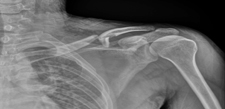

- 一旦發(fā)生嚴(yán)重的跌倒和摔傷,尤其是病人無法動彈時,最好的辦法是:... [詳細]

- 宮頸炎后為什么要盡早復(fù)位、固定?

- 當(dāng)發(fā)生宮頸炎后,一定要將病人迅速送醫(yī)院,盡早給予復(fù)位固定。因為... [詳細]